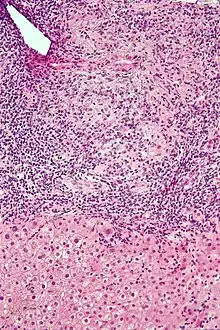

Intermediate-magnification micrograph of PBC showing bile duct inflammation and periductal granulomas, liver biopsy, H&E stain

On microscopic examination of liver biopsy specimens, PBC is characterized by chronic, nonsuppurative inflammation, which surrounds and destroys interlobular and septal bile ducts. These histopathologic findings in primary biliary cholangitis include:[32]

- Inflammation of the bile ducts, characterized by intraepithelial lymphocytes

- Periductal epithelioid granulomas.

- Proliferation of bile ductules

- Fibrosis (scarring)